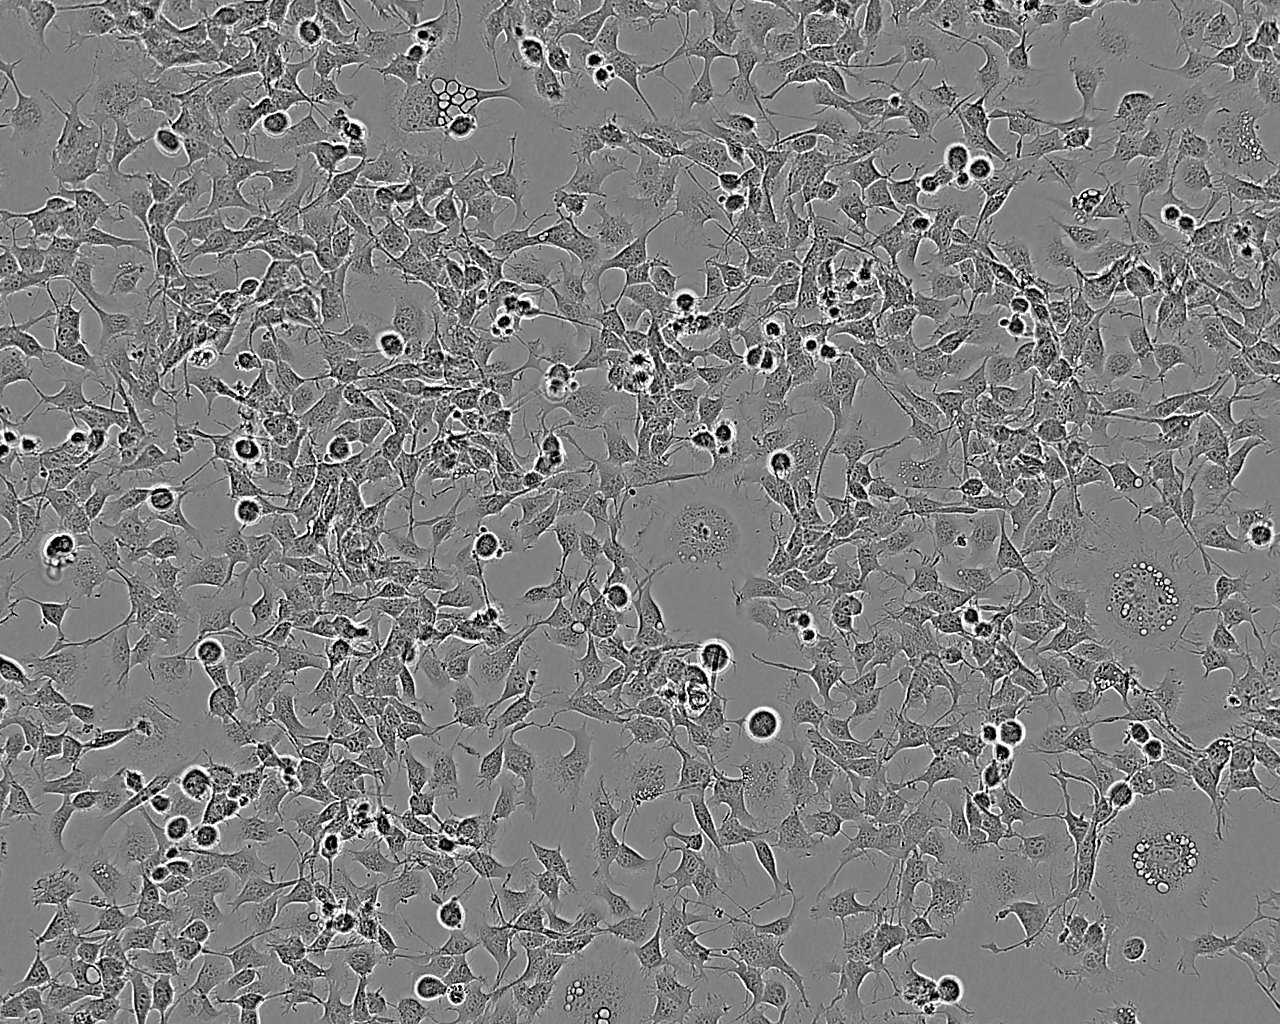

细胞形态:上皮细胞样

细胞生长:贴壁

细胞生长特性:贴壁生长